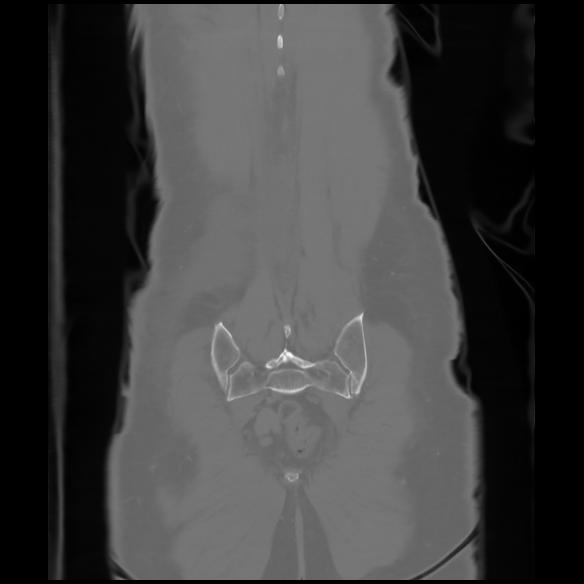

6 CUERPO,CE,Coronal,3.000,CUERPO,Coronal,